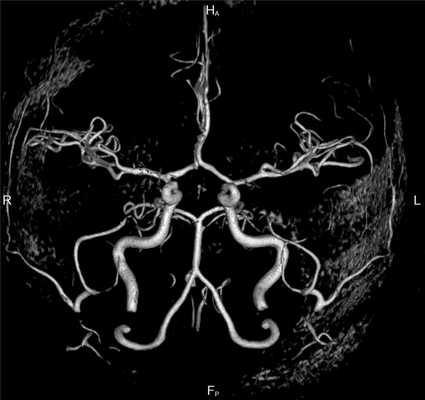

Аневризма (стрелка) на снимке МРТ головного мозга (А) и в режиме ангиографии (Б)

При цереброваскулярных заболеваниях процедура визуализирует следующие патологические изменения сосудов:

- стенозы, окклюзии кровеносного канала;

- истончение, выпячивание стенки артерии на ограниченном участке;

- эмболии различной природы (газовые, тромботические, паразитарные и пр.);

- утолщение, расслоение артериальной стенки при воспалительных процессах;

- сосудистые опухоли;

- внешнюю (экстравазальную) компрессию тканями новообразования, рубцами, окружающими структурами;

- разрывы сосудистой стенки;

- дегенеративные изменения с прорастанием соединительной ткани в просвет артерии;

- пристеночные холестериновые отложения (бляшки);

- патологические соединения (анастомозы);

- смещение кровеносного русла относительно окружающих тканей;

- аномальные петли, изгибы сосуда и пр.